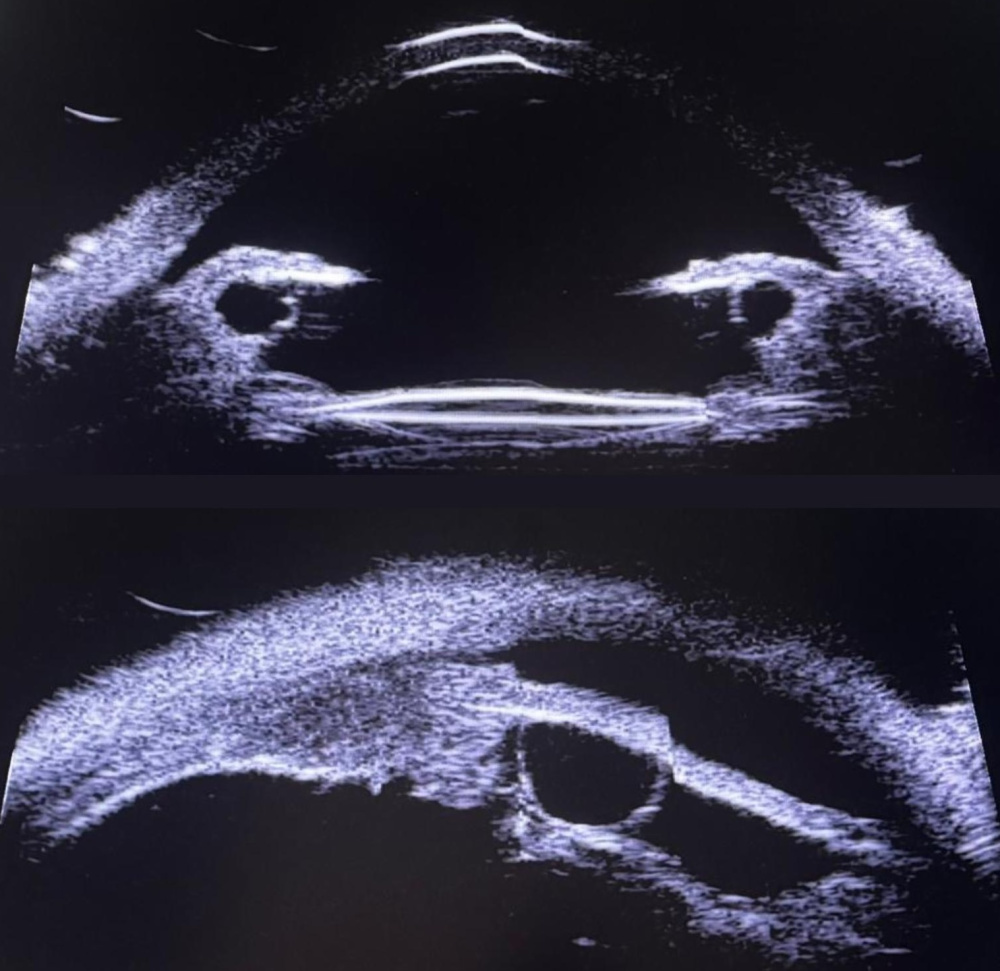

Título: Unmasking the Uvea: BDUMP as a Rare Cause of Glaucoma

Autor: Mariana Salsa Castelo

Coautores: Susana Penas; Joana Araújo.

Instituição: Unidade Local de Saúde São João, Porto, Portugal

Descrição: UBM showing diffuse ciliary body thickening and sulcus cysts. This characteristic finding was pivotal in unmasking BDUMP as the cause of secondary glaucoma, correlating the anterior uveal expansion with the posterior segment changes.